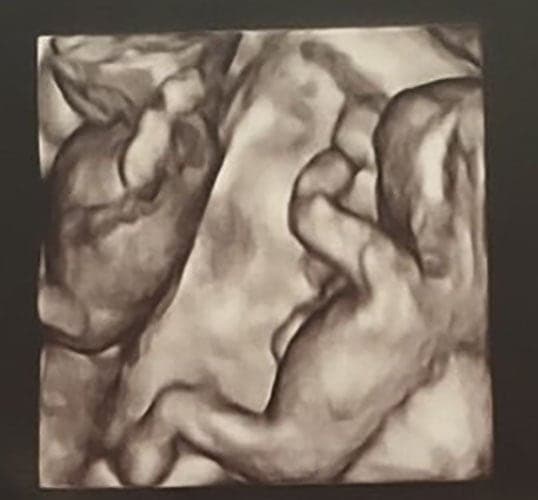

Ultraschallbilder aus dem 3. Trimester (29. bis 40. SSW)

Im dritten Trimester der Schwangerschaft ist das Baby so groß, dass es nicht mehr komplett auf ein Ultraschallbild passt. Nun kann man wunderbare 3D-Ultraschalle des Gesichts machen. In diesem Semester nehmen die Babys nochmal rasant zu und wer Glück hat, kann auf seinem Ultraschall schon erste Gesichtszüge erkennen.